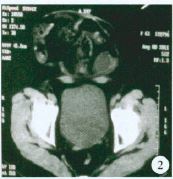

术中见:①疝囊位于耻骨上约5 cm,约15 cm×15 cm×15 cm 大,疝囊颈约12 cm×10 cm×5 cm 大(腹膜明显增厚),疝囊内见大量脓性渗出,疝内容物为嵌顿回肠(长约60 cm),充血水肿明显,色暗,较多脓苔附着;距回盲部约50 cm 处小肠与疝囊底致密粘连,包裹并形成梗阻,可见斑片状坏疽穿孔,近段小肠扩张,积气及积液(图3)。②腹、盆腔各间隙可见大量脓性渗出约400 ml,部分空肠呈“U”状与上腹部切口下致密粘连(图4)。③结肠腔内大量干结大便。

图 4 疝内容物为嵌顿回肠,长约60 cm,充血水肿明显,局部可见坏疽穿孔,部分空肠呈“U”状与上腹部切口下致密粘连